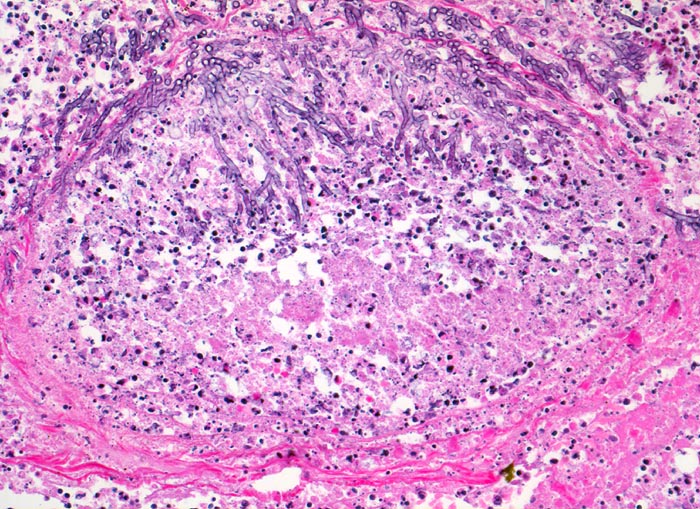

PathoPic – image database / PathoPic ID 4824 - Aspergilluspneumonie

Aspergilluspneumonie

Gewebsnekrose durchsetzt von zerfallenden neutrophilen Granulozyten (die schwarzen Punkte entsprechen den Kerntrümmern der neutrophilen Granulozyten). In der Nekrose sind schlanke Pilzhyphen mit 45° Verzweigungen erkennbar.

Seit 14 Monaten bekannte chronische lymphatische Leukämie behandelt mit Chemotherapie. Der Patient entwickelt unter Therapie eine Pneumonie und verstirbt an einer Pilzsepsis.